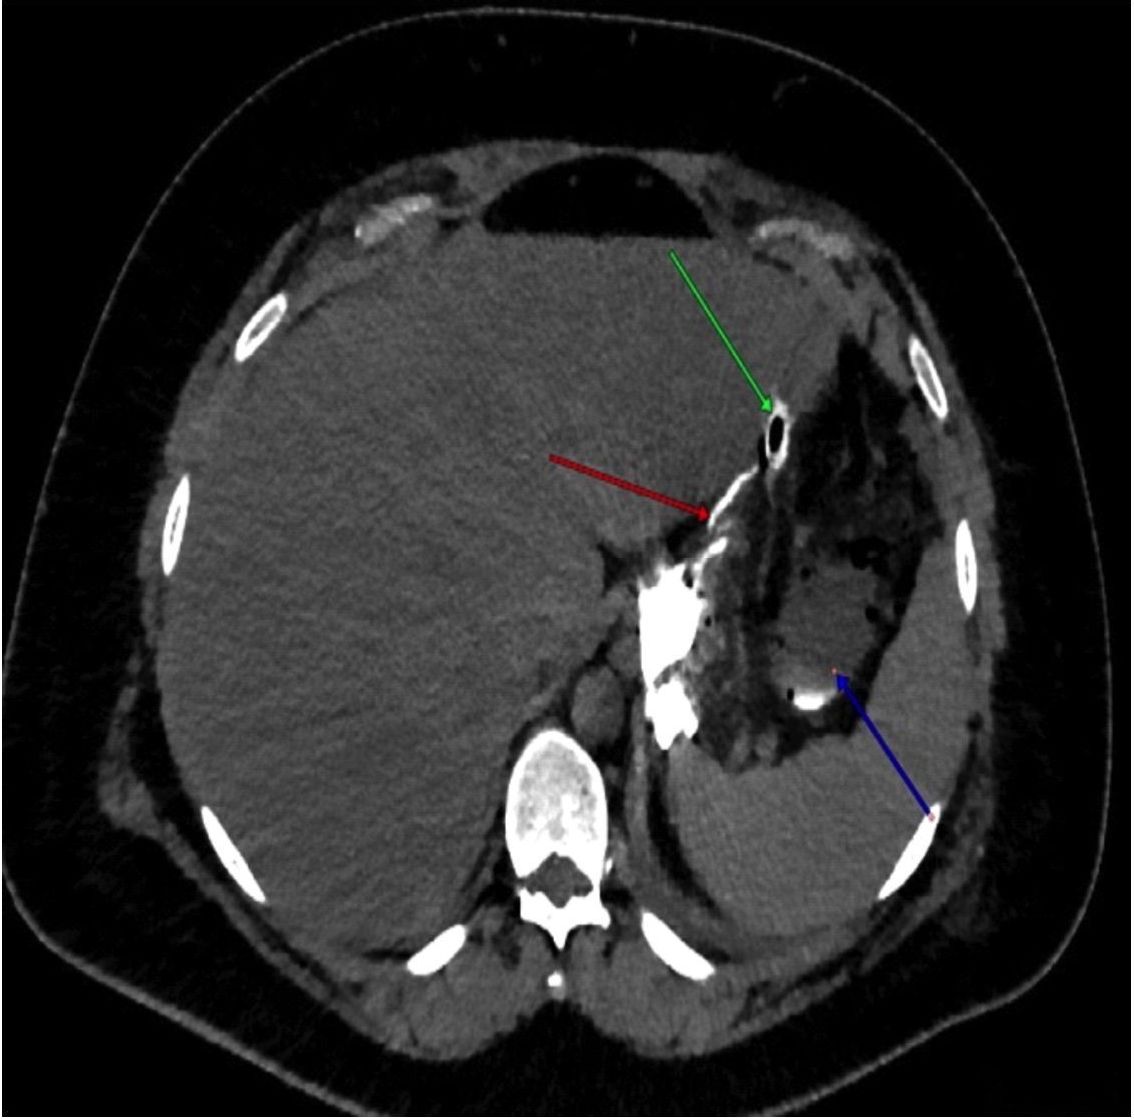

Однако на следующие сутки зафиксирован нейтрофильный лейкоцитоз: лейкоциты 19,41 · 109/л (референс: 4,5–11,0), нейтрофилы 18,8 · 109/л (референс: 1,56–6,13), лимфоциты 0,31 · 109/л (референс: 1,18–3,74), моноциты 0,3 · 109/л (референс: 0,4–1,1), и повышение уровня СРБ до 85 мг/мл (референс: 0–5), в связи с чем выполнена компьютерная томография (КТ) брюшной полости с пероральным и внутривенным контрастированием. В поддиафрагмальном пространстве слева вблизи кардиального жома обнаружено отграниченное скопление жидкости 7,5 × 6 × 11 см, со следами контрастного вещества, что свидетельствовало о несостоятельности скрепочного шва в области кардиального отдела культи желудка (рис. 2).

Рис. 2. Мультиспиральная компьютерная томография брюшной полости с внутривенным и пероральным контрастированием. Фронтальная MPR-реконструкция. Дефект в области скрепочного шва (зеленая стрелка) с контрастированием хода в левом поддиафрагмальном пространстве (красная стрелка) и затеком контрастной взвеси в отграниченное жидкостное скопление (синяя стрелка)